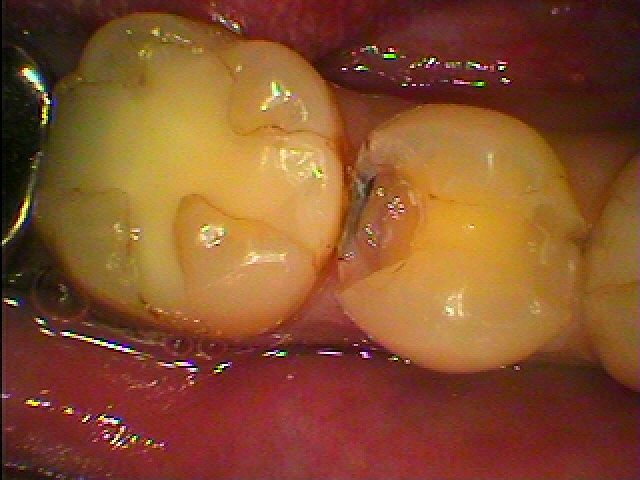

治療前になります